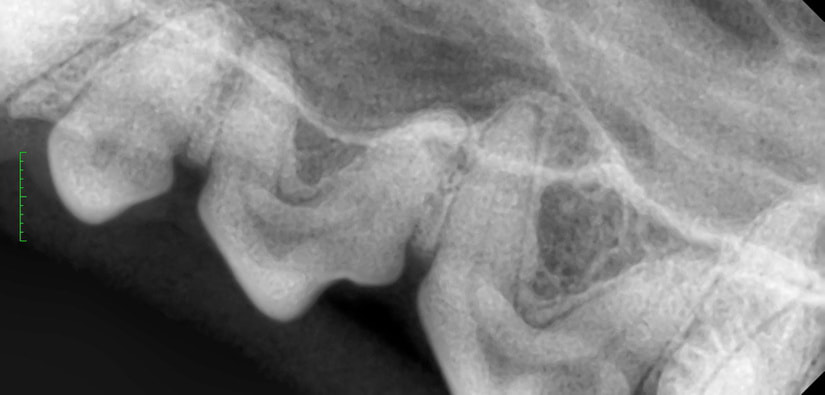

歯のX線撮影を行います。

X線写真で歯周病の程度を判断します。